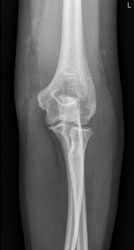

Eine 37 Jahre alte Frau stürzt auf dem Eis zu Boden und stützt sich mit dem linken Arm noch ab. Wegen Schmerzen im linken Ellbogen geht sie zum Arzt, welcher das folgende Röntgenbild macht.

Der erstbehandelnde Arzt sieht auf dem Röntgenbild keine Fraktur und verordnet der Patientin Schmerzmittel. Weil die Schmerzen aber nicht bessern, meldet sich die Patientin wieder und das Röntgenbild wird noch einmal beurteilt:

Ellbogen ap

Wie beurteilen Sie das Röntgenbild?